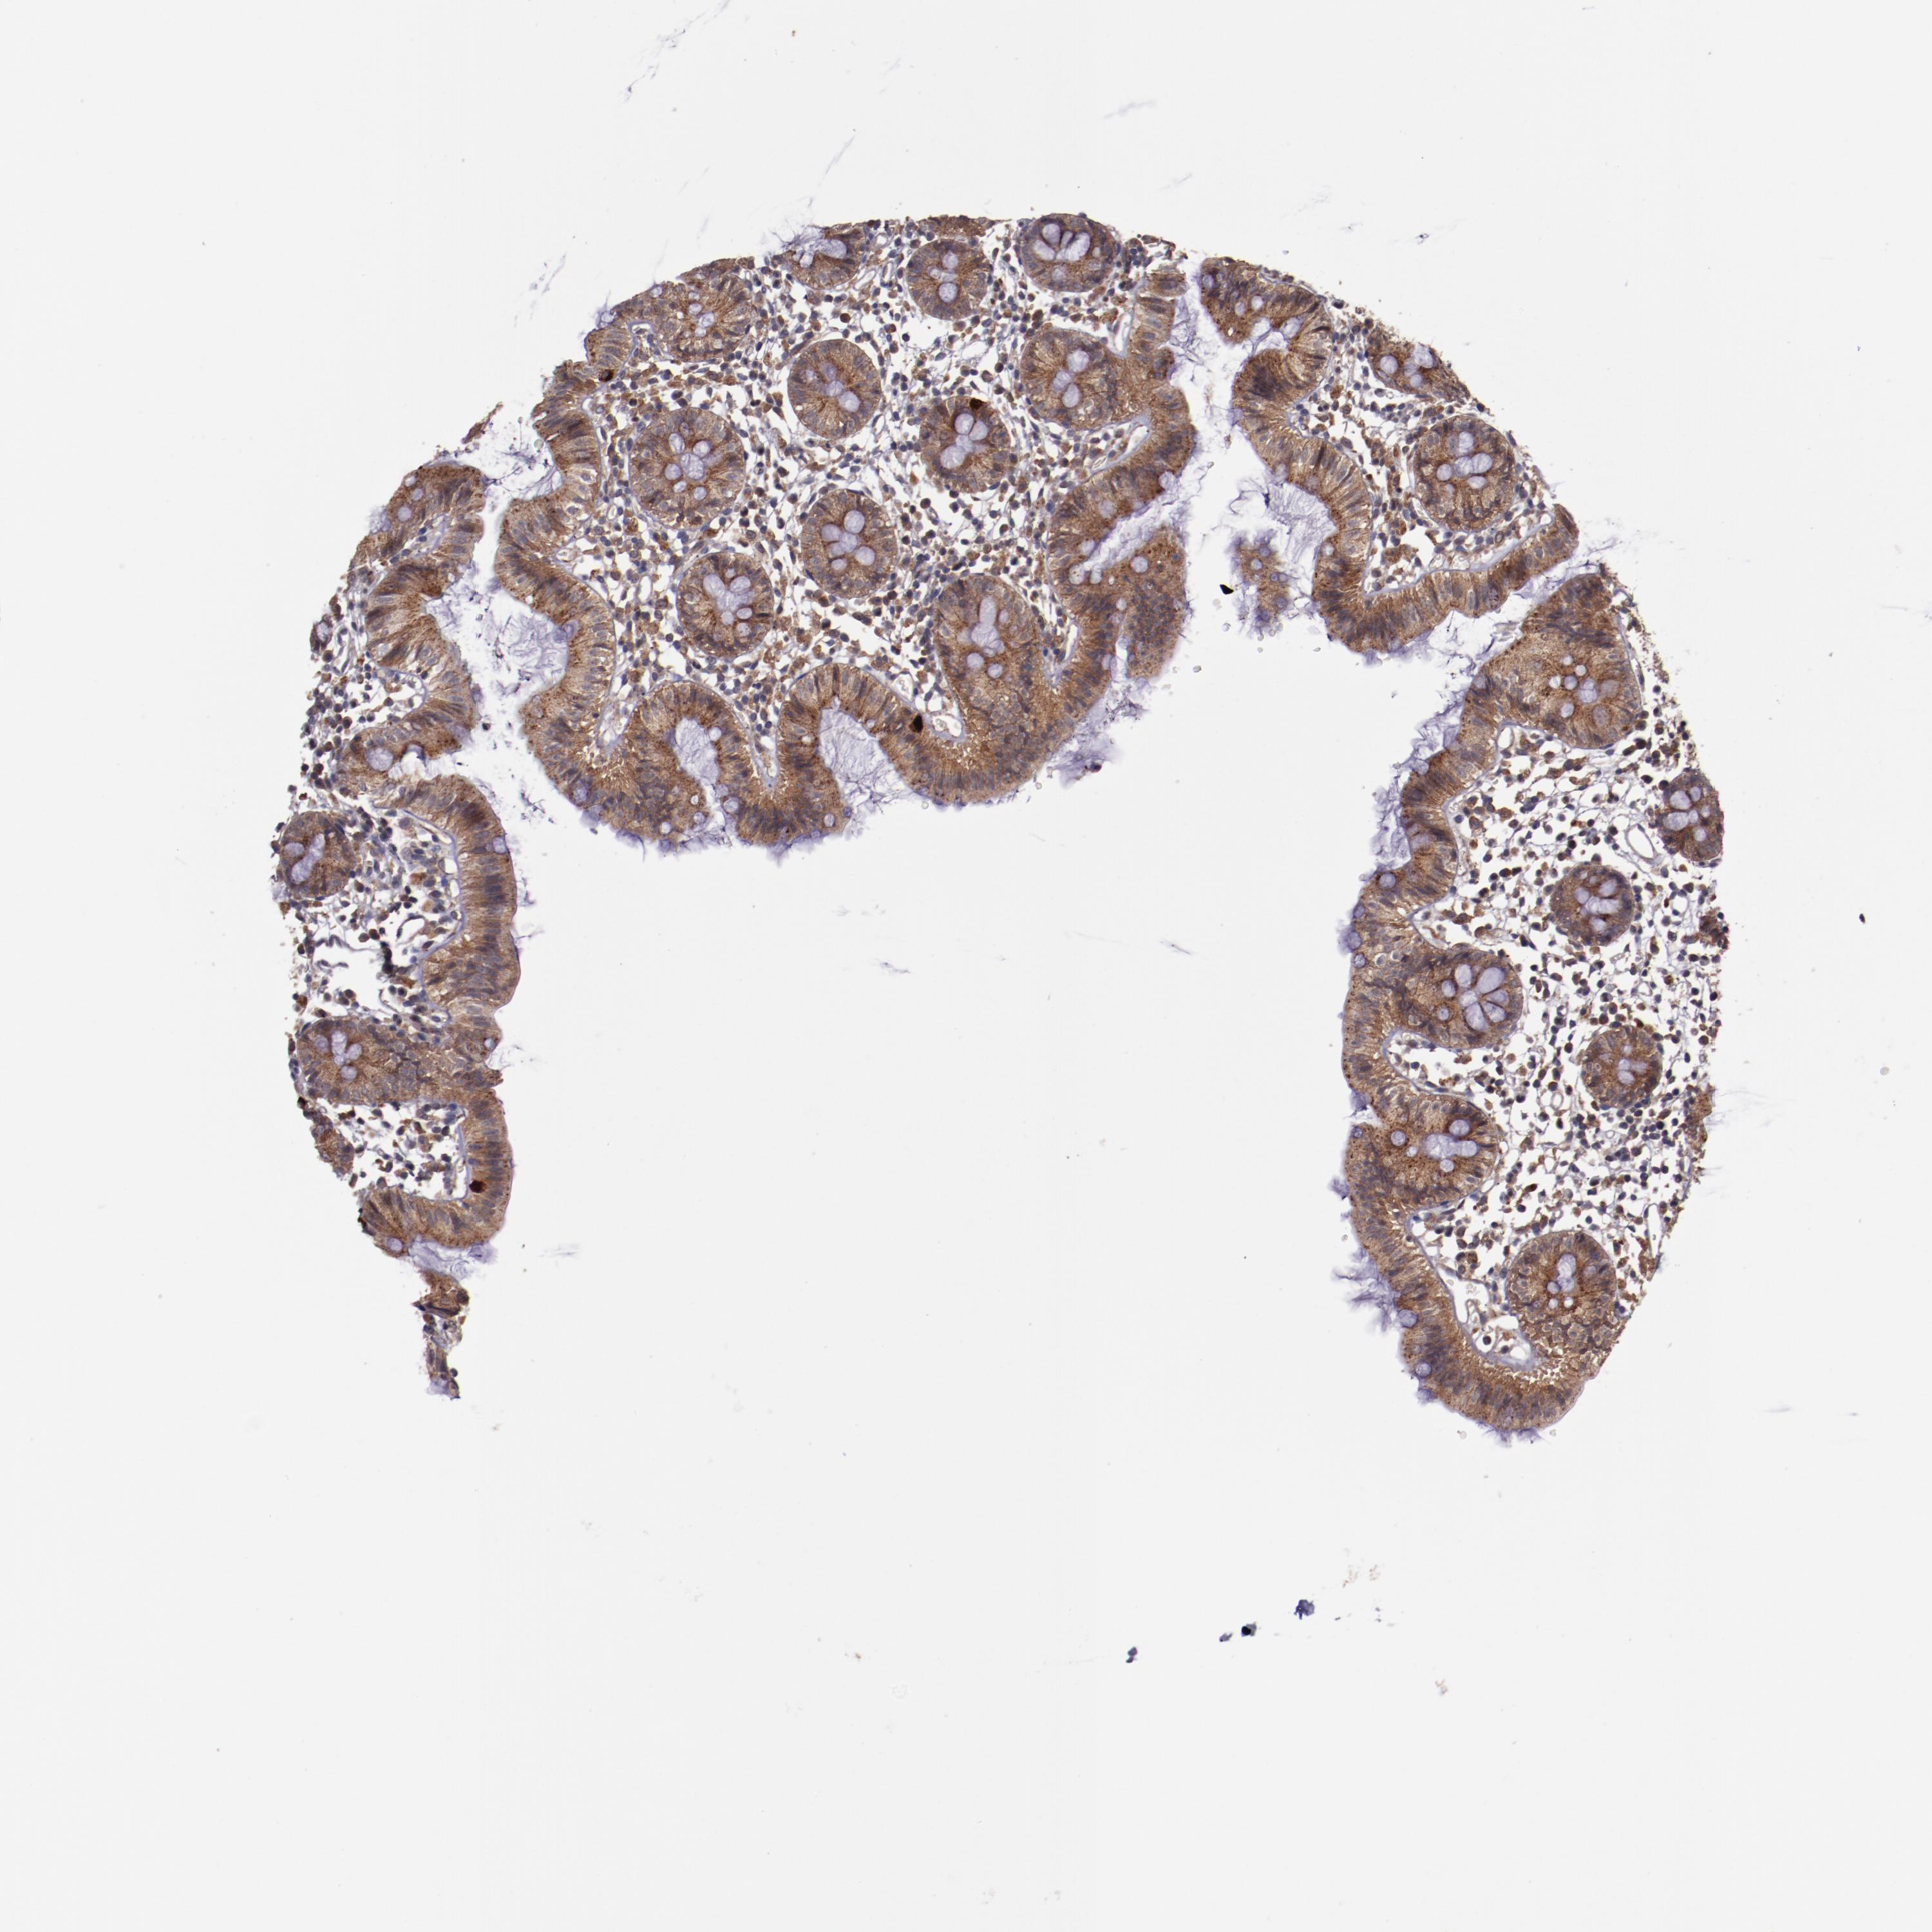

Antibody staining in the annotated cell types in the current human tissue is reported as not detected, low, medium, or high. This score is based on the staining intensity and fraction of stained cells.